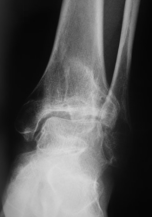

目前应用最广的是踝关节骨关节炎分期为Takakura-Tanaka分期:

0期:踝关节平行,无关节炎征象;

Ⅰ期:踝关节平行,无关节间隙狭窄,有早期软骨下骨硬化或骨赘形成;

Ⅱ期踝内侧关节间隙狭窄,无软骨下骨接触;

Ⅲ期又可分Ⅲa期和Ⅲb期:

Ⅲa期 踝内侧间隙消失,软骨下骨接触面局限于内侧;

Ⅲb期 踝软骨下骨接触延伸至距骨穹窿部;

Ⅳ期 踝关节间隙消失伴全部软骨下骨接触。

影像学检查:最重要的诊断依据:如X片检查、CT检查、MRI检查、超声波检查等,其中X片及CT对诊断尤为重要。

X片:检查可以显示关节间隙狭窄、骨赘形成、软骨下骨硬化等特征性表现;